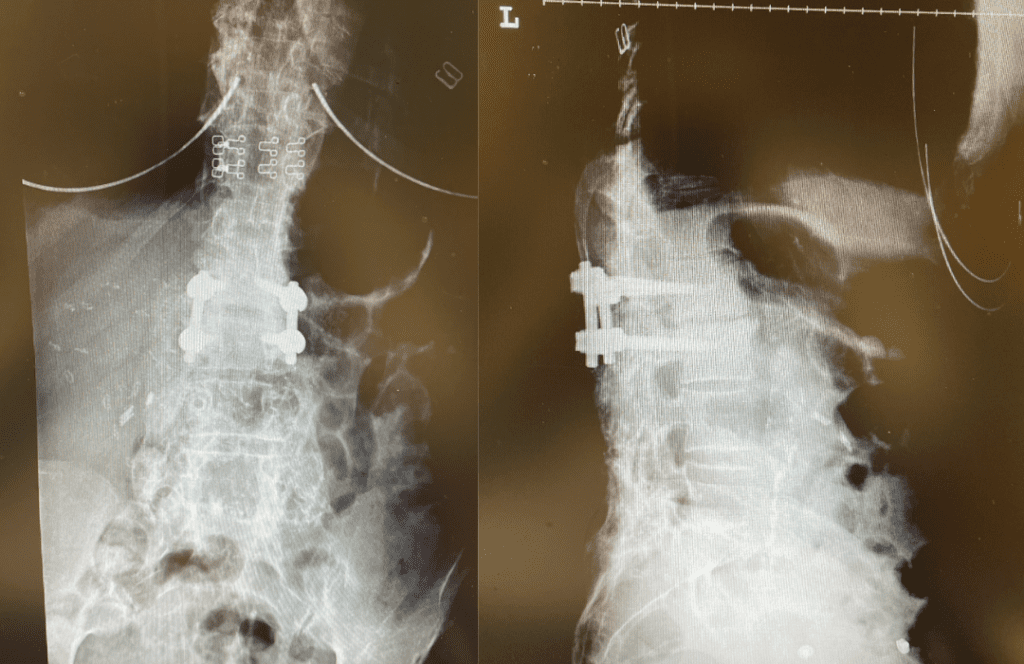

This 62-year-old female presents with chronic intractable low back pain with radiation down the front of her thighs. The patient had had two prior fusion surgeries: She initially had an L4-S1 fusion twelve years prior and a subsequent revision extension of her fusion at L3-4 that she had three years prior. She had a long-term history of smoking. She had mild hip flexor weakness, right greater than left. Imaging studies revealed next segment degeneration and stenosis at L2-3 (Figs. 1a and 1b and 2).

Figures 1a and 1b. Sagittal T2 MRIs of the lumbar spine demonstrating L2-3 stenosis after L3-4 instrumented fusion.